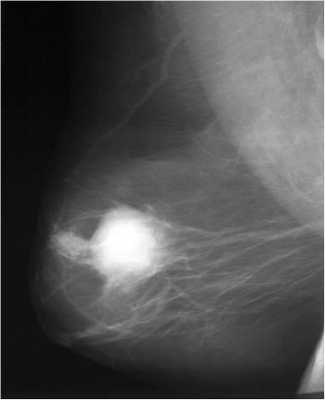

Для выявления злокачественных опухолей молочной железы существует определенный алгоритм диагностики, и его первичный элемент — маммографический скрининг. Чувствительность этого метода диагностики для опухолей от 2 мм до 5 мм составляет около 85%. Маммографическое исследование выполняют в двух проекциях.

При стандартной маммографии карцинома в протоке не всегда обнаруживается, зачастую о её существовании догадываются по расширению протока и его деформации. О злокачественной природе свидетельствует скопление глыбок кальция в извитых сосудах опухоли, но обызвествление присутствует не всегда.

Световое сканирование или диафаноскопия молочной железы в инфракрасном свете не имеет самостоятельного значения, исследование безвредно для женщины, но для диагностики недостаточно только констатации факта патологических изменений в молочной железе. Такой же малой информативностью обладает и термография, показывающая любую патологию железы с расплывчатой локализацией. Обе методики дают красочные картинки действительности, но не отвечают на вопрос «что и где».

Оптимальна дуктография — рентгеновское исследование с нагнетанием контрастного вещества в млечные протоки, позволяющее определить точную локализацию и размер, но не морфологию новообразования.